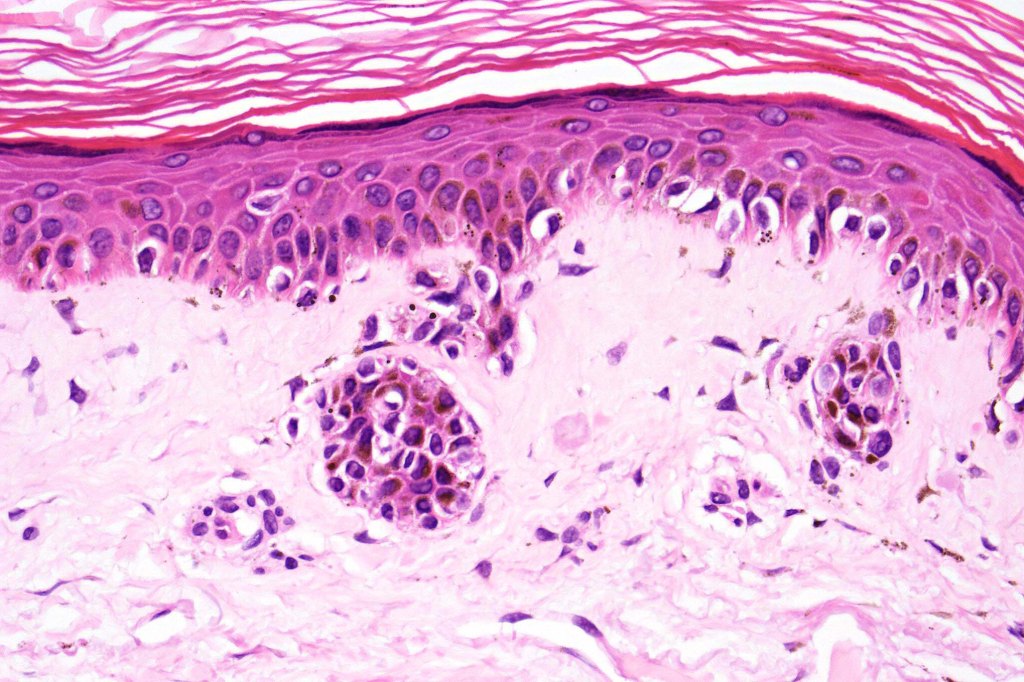

Histological features

- A broad lentiginous proliferation of atypical melanocytes unasscoiated with any loss of the rete ridges

2. Melanocytes generally small, epithelioid (rather than spindled) with either vesicular nuclei and prominent nucleoli or are hyperchromatic.

3. The cells can be present singly, in short pallisades or can extend along a large section of epidermis

7. Fibroplasia not seen and elastosis is either mild or absent

8. An invasive component may be present